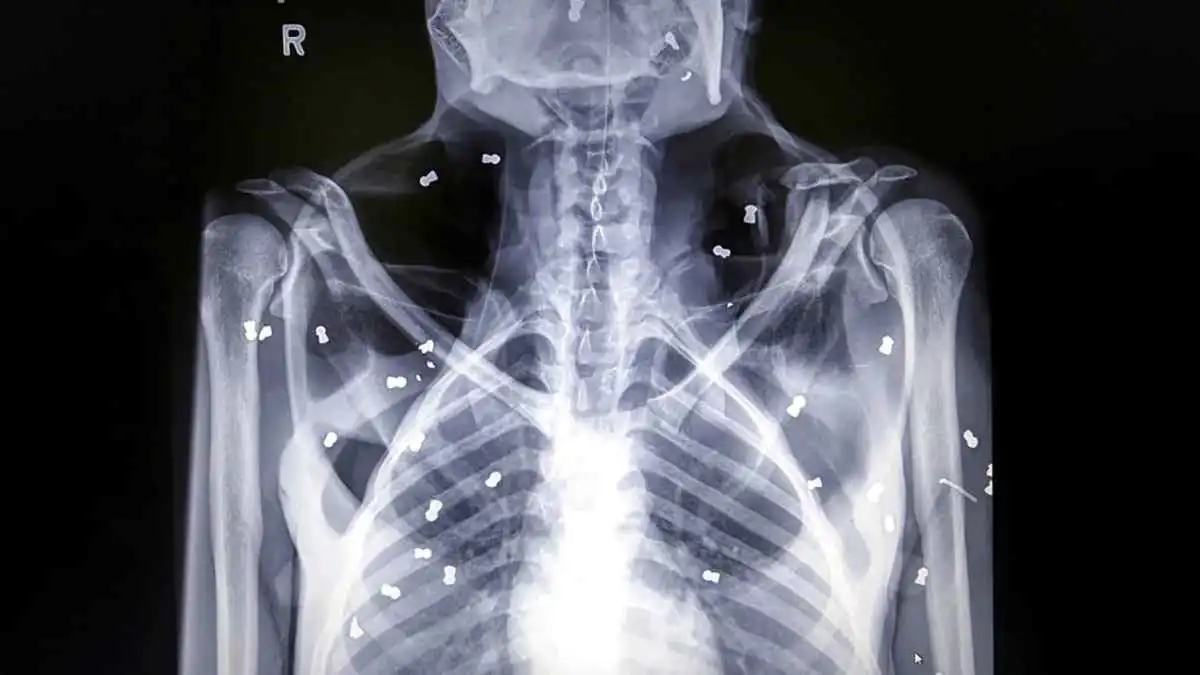

صورة أسعة تظهر كسور العظام - تعبيريةالمصدر: (أ ب)